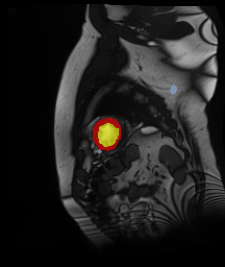

Medical data often exhibits long-tail distributions with heavy class imbalance, which naturally leads to difficulty in classifying the minority classes (i.e., boundary regions or rare objects). Recent work has significantly improved semi-supervised medical image segmentation in long-tailed scenarios by equipping them with unsupervised contrastive criteria. However, it remains unclear how well they will perform in the labeled portion of data where class distribution is also highly imbalanced. In this work, we present ACTION++, an improved contrastive learning framework with adaptive anatomical contrast for semi-supervised medical segmentation. Specifically, we propose an adaptive supervised contrastive loss, where we first compute the optimal locations of class centers uniformly distributed on the embedding space (i.e., off-line), and then perform online contrastive matching training by encouraging different class features to adaptively match these distinct and uniformly distributed class centers. Moreover, we argue that blindly adopting a constant temperature $\tau$ in the contrastive loss on long-tailed medical data is not optimal, and propose to use a dynamic $\tau$ via a simple cosine schedule to yield better separation between majority and minority classes. Empirically, we evaluate ACTION++ on ACDC and LA benchmarks and show that it achieves state-of-the-art across two semi-supervised settings. Theoretically, we analyze the performance of adaptive anatomical contrast and confirm its superiority in label efficiency.

翻译:医学数据经常呈现长尾分布和重度类别不平衡,这自然导致在对少数类别(即边界区域或罕见目标)进行分类时出现困难。最近的研究在长尾情况下通过装备医学影像的无监督对比标准,明显改进了半监督医学图像分割。然而,在标记的数据部分中,类别分布也极为不平衡,因此它们的表现如何仍不清楚。在本研究中,我们介绍一种采用自适应解剖对比度改进的对半监督医学分割行动的框架(ACTION++)。具体来说,我们提出了一种自适应监督对比损失,它首先在嵌入空间上计算出不同类别的优化位置(即离线),然后通过鼓励不同类别之间的特征与这些不同和均匀分布的类别中心相适应的在线对比匹配训练来进行自适应匹配。此外,我们认为,在长尾医疗数据中盲目采用常温度$\tau$不是最优的,因此通过一个简单的余弦计划来使用动态$\tau$来产生更好的多数类别和少数类别之间的分离。在实证方面,我们在ACDC和LA基准测试中评估ACTION++,并展示了其在两种半监督设置下的最新成果。从理论上讲,我们分析了自适应解剖对比度的性能,并证实了它在标签效率上的优越性。